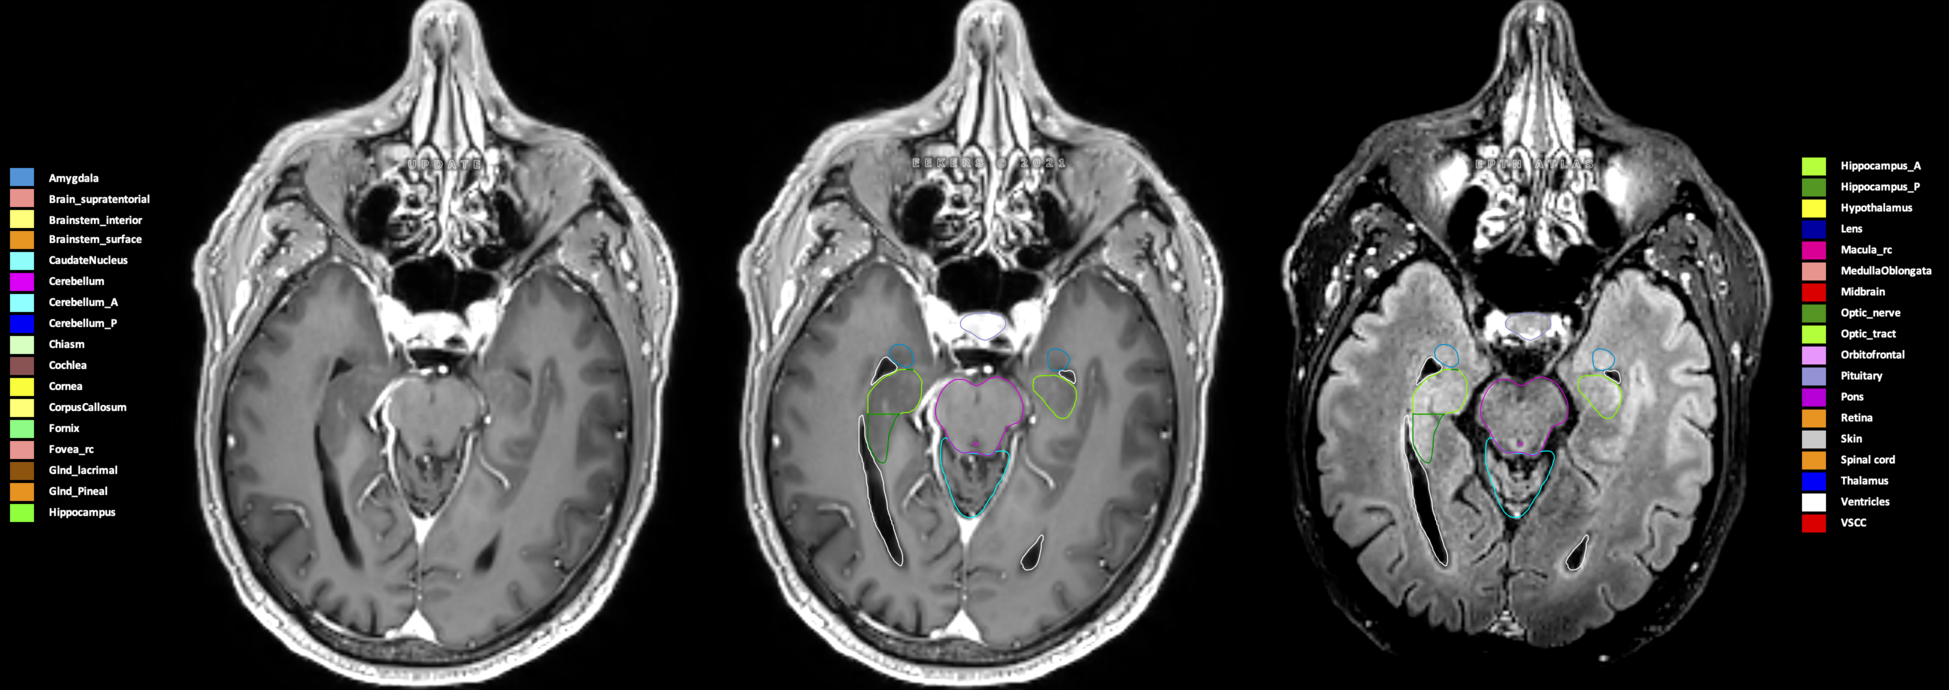

Eekers et al. have published an international neurological atlas for contouring of organs at risk in consensus with the European Particle Therapy Network (EPTN) in 2018 and an update in 2021. The purpose of this consensus atlas is to decrease inter- and intra-observer variability in delineating OARs relevant for neuro-oncology.

Included are all OARs known to be relevant for radiation-induced toxicity in neuro-oncology: brain, brainstem (midbrain, pons, medulla oblongata), chiasm, cerebellum (anterior & posterior), cochlea, cornea, hippocampus (anterior & posterior), hypothalamus, lens, lacrimal gland, optic nerve, pituitary, skin, and vestibular & semicircular canals. To further facilitate research on cognition, vision and radiological changes after irradiation of the brain, potential clinically-relevant OARs are included: amygdala, caudate nucleus, cerebellum (anterior & posterior), corpus callosum, fornix, macula, optic tract, orbitofrontal cortex, periventricular space (PVS), pineal gland, and thalamus.

Three-dimensional delineation of the 25 consensus OARs for neuro-oncology are shown on CT (WW/WL 120/40, 3000/600), 3T MR images, (T1Gd, T2FLAIR 1mm) and 7T MR (MP2RAGE 0.7 mm). All are presented in transversal, sagittal and coronal view.